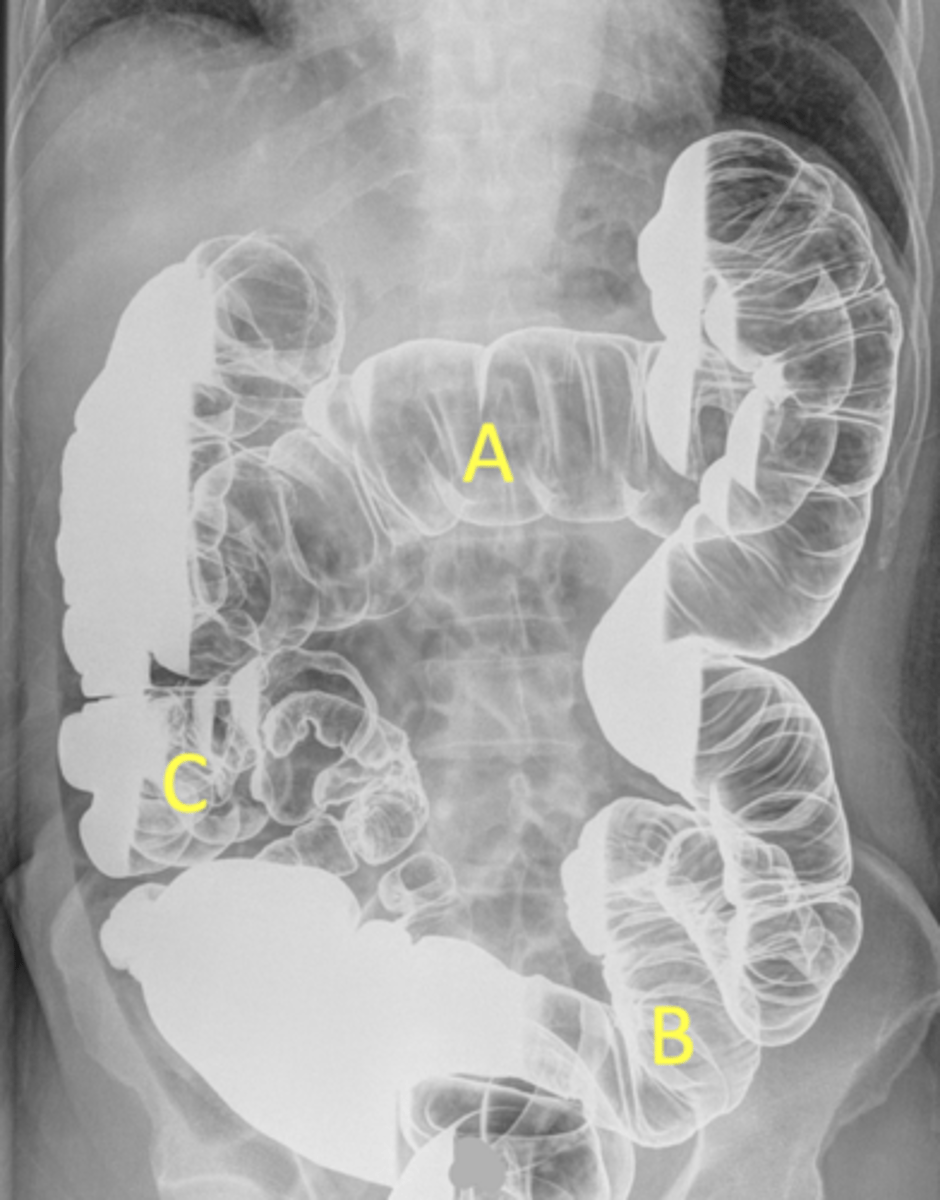

A - Transverse colon

B - Sigmoid colon

C - Cecum/ascending colon/iliocecal junction

pt is on their side due to seeing white fluid and haustra

Label the radiograph